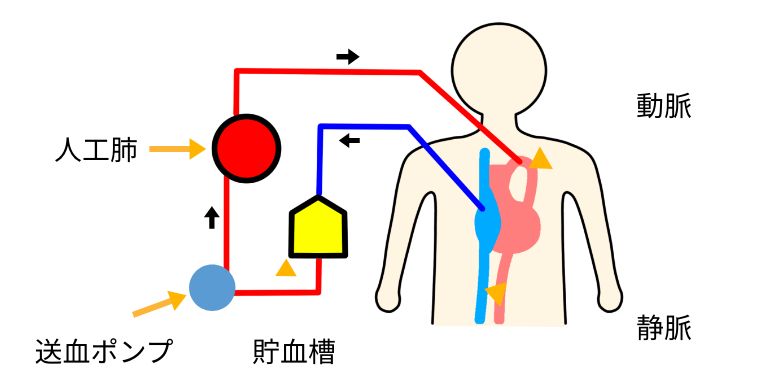

心臓の手術では、心臓が動いて血液が循環したまま細かな手術をする事は難しく、心臓を停止して手術を行う場合があります。その際に使用するのが人工心肺と呼ばれる装置です。動脈と静脈に管を挿入してローラーポンプという装置を使って全身に血液を送っています。静脈血を人工肺という器械を使って二酸化炭素と栄養である酸素を交換します。

人工心肺という装置を使うと、心臓や肺が働かなくとも脳などの全身の組織に必要な血液が送られるので、手術を受ける患者さんの生命を維持することができます。しかしながら、人工心肺の長時間の使用により、脳血管障害、肺、腎臓障害、出血傾向などの合併症が発生してしまう可能性もあります。当院では、人工心肺の専門資格を所得した経験豊富な臨床工学技師4名が常勤し安全第一に取り組んでおります。